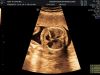

- Voluson E8 giúp đơn giản hóa quá trình quét, cho hình ảnh có chiều sâu và sắc nét nhờ công nghệ HDlive, tập trung vào chi tiết hình ảnh đảm bảo chẩn đoán chính xác.

- Đánh giá dễ dàng và toàn diện về kích thước, hình dạng và sức co bóp của tim thai từ chế độ xem 4 buồng, cho phép kiểm tra sức khỏe của thai nhi chính xác nhất

- Độ phân giải tương phản nâng cao với hiển thị mô, xương và chi tiết vượt trội với công nghệ đầu dò XDclear ™, Omniview đảm bảo quét được với cả những bệnh nhân khó siêu âm, cho hình ảnh tối ưu ngay cả khi thai nhi chuyển động

- Công nghệ Sonography cho phép đo, phân tích độ mờ da gáy, độ mờ nội sọ hỗ trợ chẩn đoán dị tật bẩm sinh như down, vô sọ...